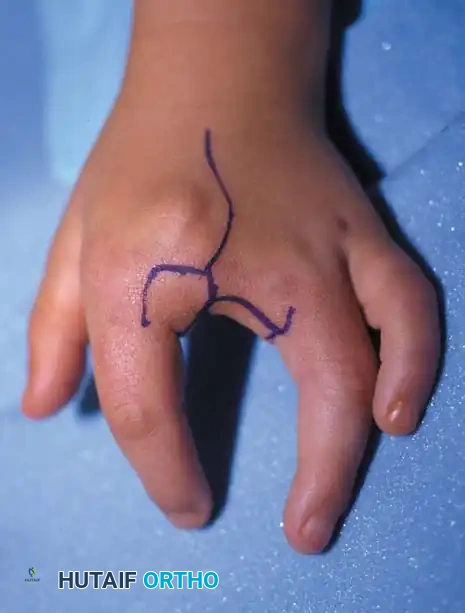

Surgical Interventions in Transverse Deficiencies

Surgical indications for transverse deficiencies are exceedingly rare. Epps, Burkhalter, and McCollough reported that out of 1,077 children